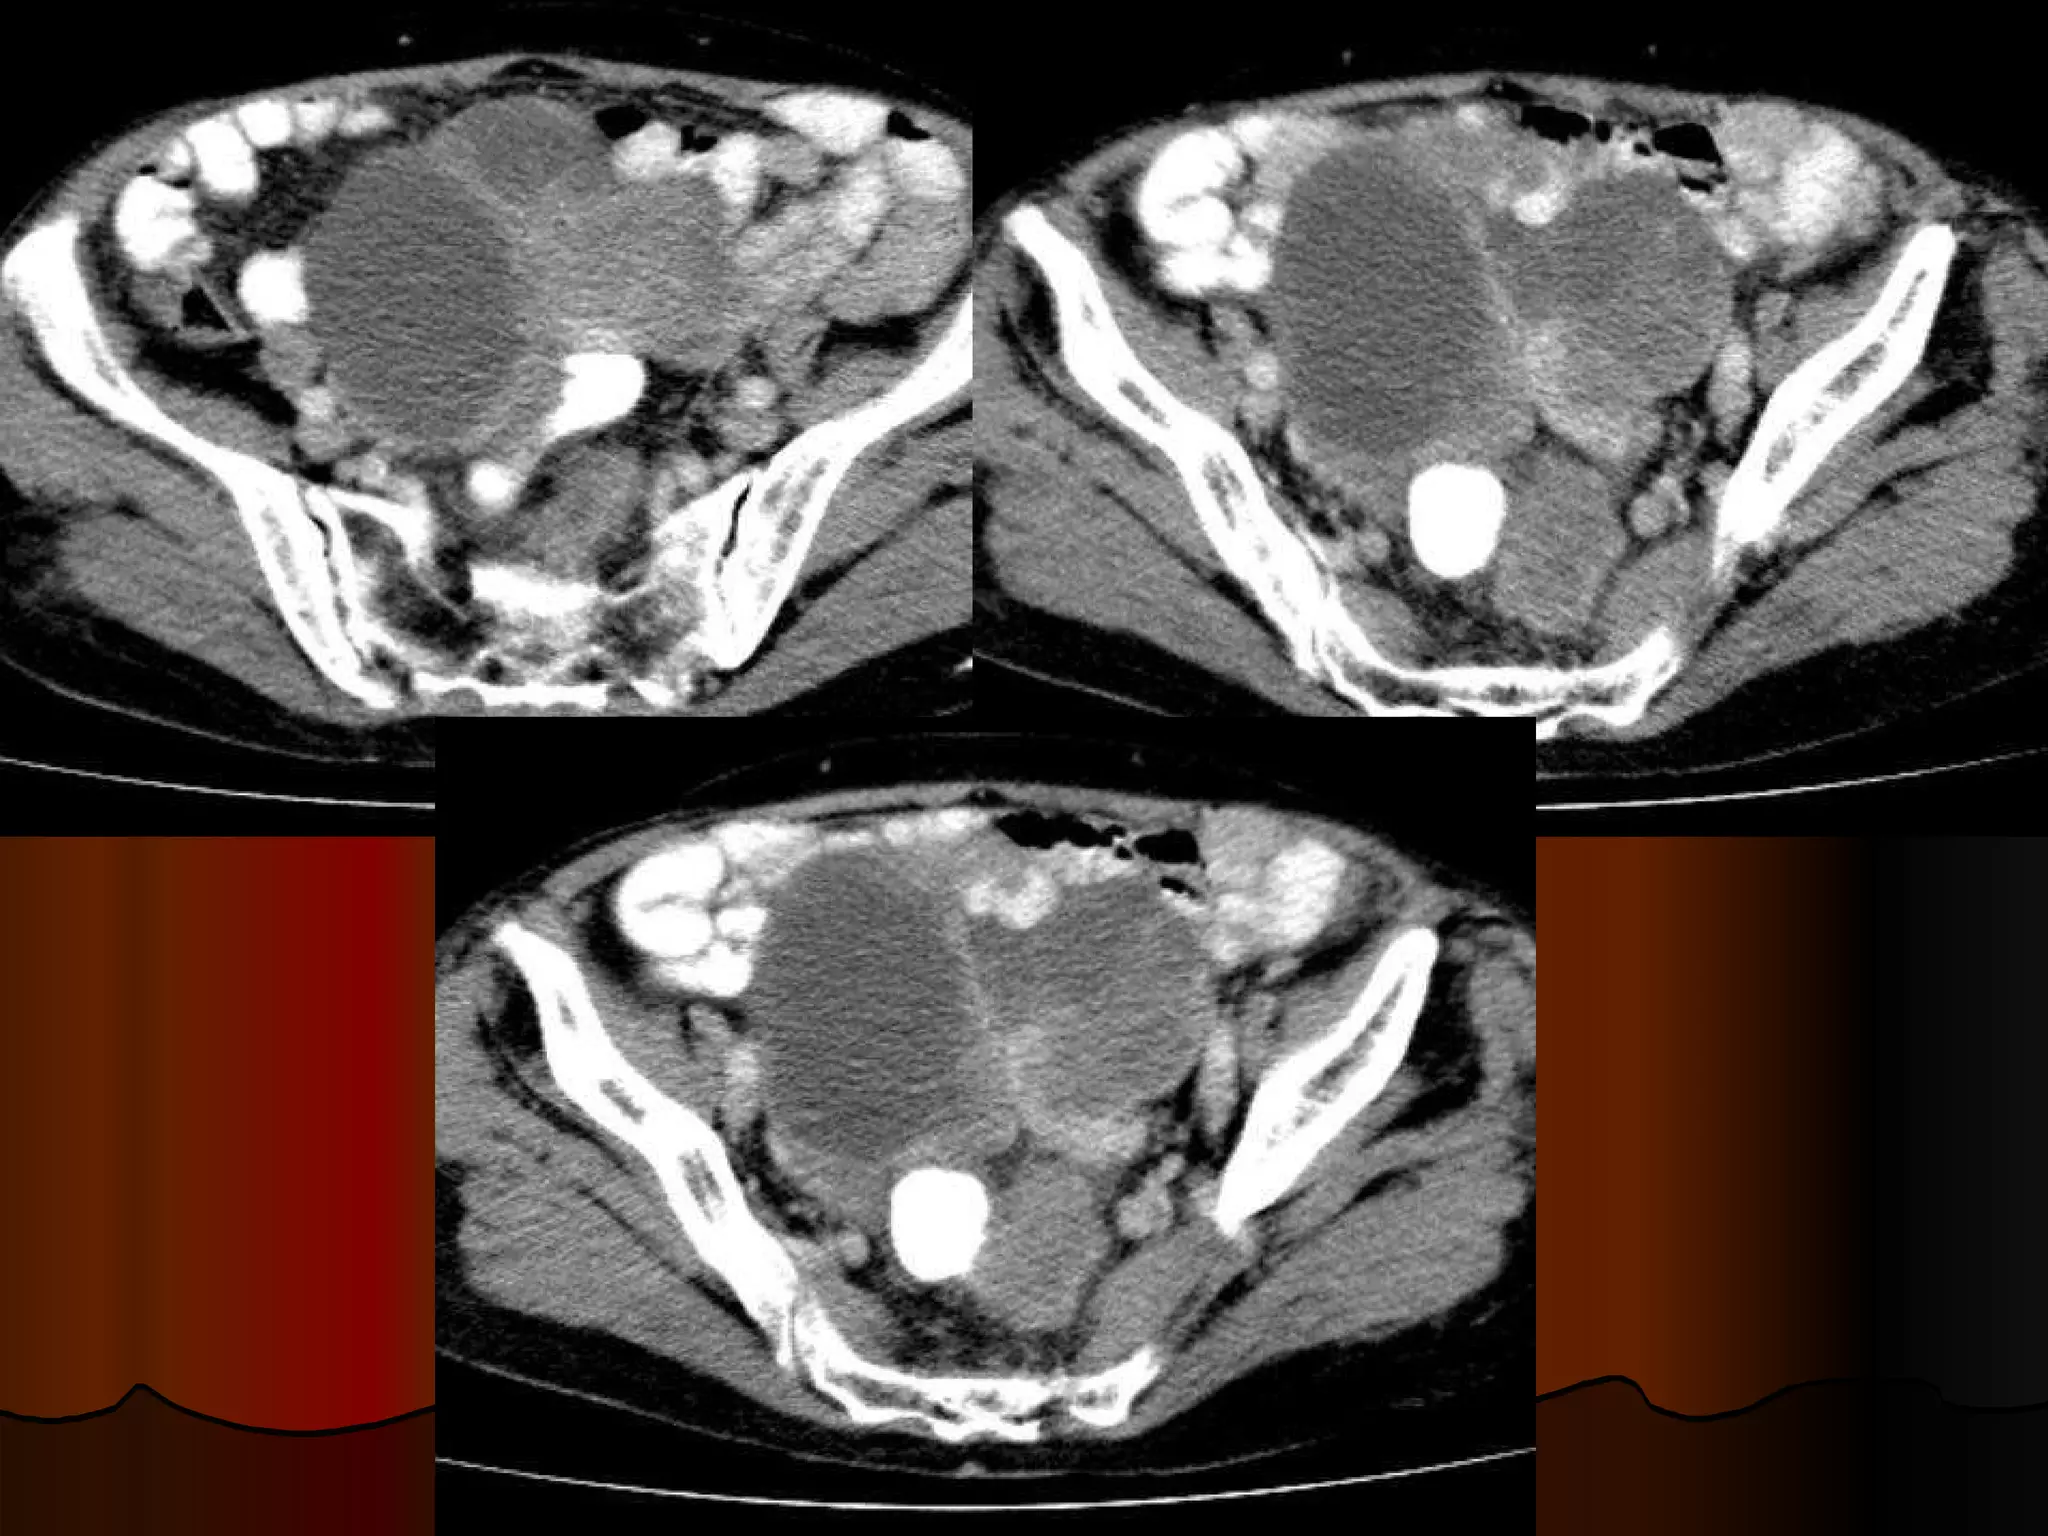

Случай 1. - женщина, 60 лет, госпитализирована в отделение сосудистой хирургии с диагнозом острый тромбоз левой бедренной артерии при скриннинговом УЗИ брюшной полости над мочевым пузырем обнаружено опухолевидное образование  из анамнеза – жалобы на боли в левой ноге, абдоминальных болей, нарушений частоты или консистенции стула не предъявляет при пальпации  объемное эластичное подвижное образование в гипогастральной зоне, чувствительное при глубокой пальпации. В анализах – умеренная гипохромная анемия. Гинекологический статус – без патологических находок. Ирригография– без патологических находок.

КТ-находки Образование с признаками экспансивного роста Локализация -  интраперитонеально инфрамезентериально по срединной линии  По строению напоминает кишечную трубку с циркулярным утолщением стенок, прослеживается их слоистость, просвет выполнен воздухом и жидкостью, четкие контуры Органная принадлежность – подвздошная кишка/ брыжейка, однако не видно типично «входящей» и «отходящей» петли, скорее прилежит к протитво-брыжеечному краю Гомогенно усиливается без признаков гиперваскулярности, внутренний «слой» гиподенсный Нет признаков кишечной обструкции, реакции перифокального жира, лимфаденопатии, подвздошые сосуды не компрессированы, печень не поражена Пристеночный линейный тромб на уровне устья  общей подвздошной артерии слева

Вопросы для дискуссии Сообщение с просветом кишки - следствие некроза или естественный просвет? Почему нет признаков кишечной обструкции? Если опухоль, то какая? Возможно ли, что не опухоль, учитывая анатомическую область?

Gastrointestinal stromal tumor  ( GIST )? Гастроинтестинальные стромальные опухоли (GIST-Gastrointestinal Stromal Tumors) составляют от 0,1% до 3% от всех злокачественных новообразований желудочно-кишечного тракта Типичной локализацией GIST является желудок (60-70%), тонкая кишка (25-35%), толстая и прямая кишка (5%).  Возраст 50-70 лет Часто асимптоматичные, случайные находки, если есть симптомы – обычно это боли в животе, изъязвление, кровотечения и их осложенения.  Просвет обычно не стенозирован, поскольку длительно сохраняется эластичность кишечной трубки, в отличии от карцином обычно медленный рост, метастазируют в печень и по брыжейке Показано иммуногистохимическое исследование

Дивертикул Меккеля? конгенитальная патология,  представляет собой остаток желточного (омфаломезенетриального) протока. Частота 2—3%. Располагается на противо-брыжеечном крае подвздошной кишки в 60— 100 см от илеоцекального угла. Это истинный дивертикул, в его стенке находятся все слои кишки; могут быть и эктопированная ткань желудка, поджелудочной железы, островки толстокишечного эпителия. Обычно асимптоматичен, может осложнятся: перекрут, кишечная обструкция дивертикулит, изъязвление, кровоточение, перфорация грыжа опухолевое поражение